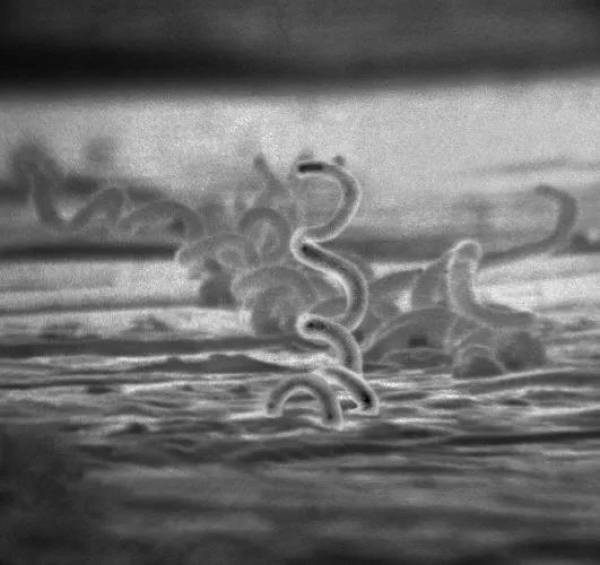

梅毒螺旋体的电镜照片。图片来源:CDC/Dr.David Cox,Public Domain